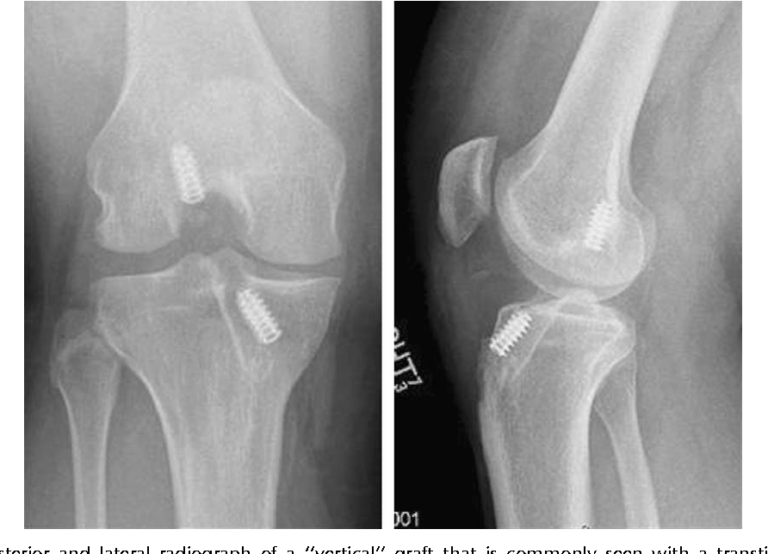

From www.researchgate.net

(PDF) Knee temperatures measured in vivo after arthroscopic ACL Heat After Acl Reconstruction This protocol is time based. Avoid applying heat to the affected area. Full recovery after acl surgery typically takes around 9 months, so have patience with yourself if you have a hard time getting back into the swing of things. Treatment aims to improve range of. First 2 weeks after acl surgery: Cleanse around the area or use a plastic. Heat After Acl Reconstruction.